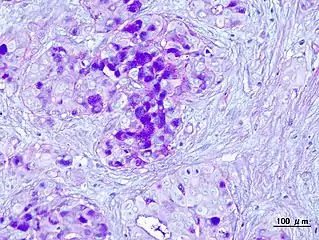

| Micrograph of a mucoepidermoid carcinoma. FNA specimen. Pap stain. | |

Mucoepidermoid carcinoma (MEC)[1] is the most common type of minor salivary gland malignancy in adults. Mucoepidermoid carcinoma can also be found in other organs, such as bronchi, lacrimal sac,[2] and thyroid gland.

Mucicarmine staining is one stain used by pathologist for detection.[3]

In terms of diagnosis we find that histological staining, radiological imaging and molecular diagnostic features all play a role in the evaluation[1] This tumor is not encapsulated and is characterized by squamous cells, mucus-secreting cells, and intermediate cells.[7]